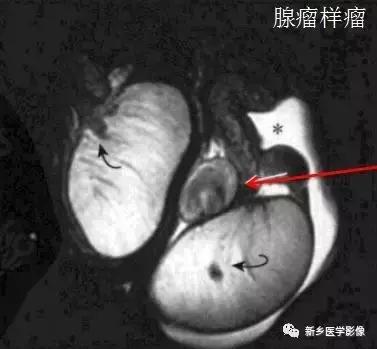

腺瘤样瘤——附睾尾或附近,T2WI信号高于附睾

乳头状囊腺瘤——良性附睾病变,可合并VHL病